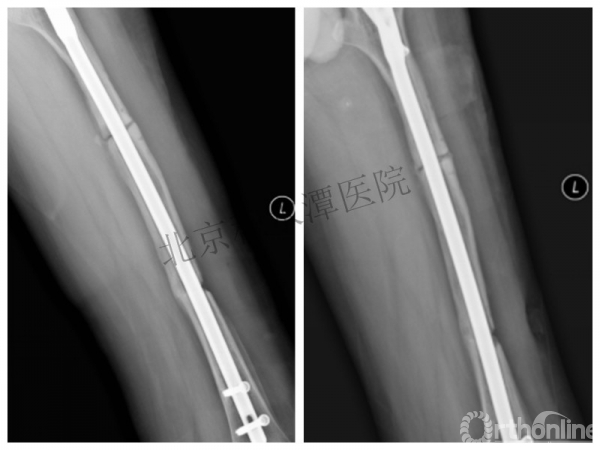

病例分享一

男孩 、5岁,初次骨折于2007年7月。

术后2年→再骨折→再次手术

钢板固定后一年

取板后再骨折→TEN

TEN取出后2个月

闭合复位再固定加尾帽

又过了4年!时间来到2015年

一年以后顺利愈合,实则危机四伏

数月后再骨折!牵引!

髋人字支具

外固定架术后一年

整整11年!是否治疗终结?

病人的付出?医生当反思!